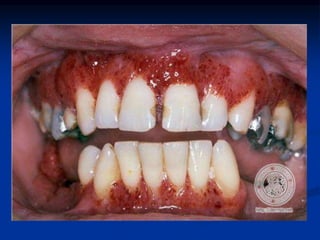

SARCOMA DE KAPOSI

SARCOMA DE KAPOSI CON INFECCIÓN POR

CANDIDA SP

SARCOMA DE KAPOSI FORMA NODULAR